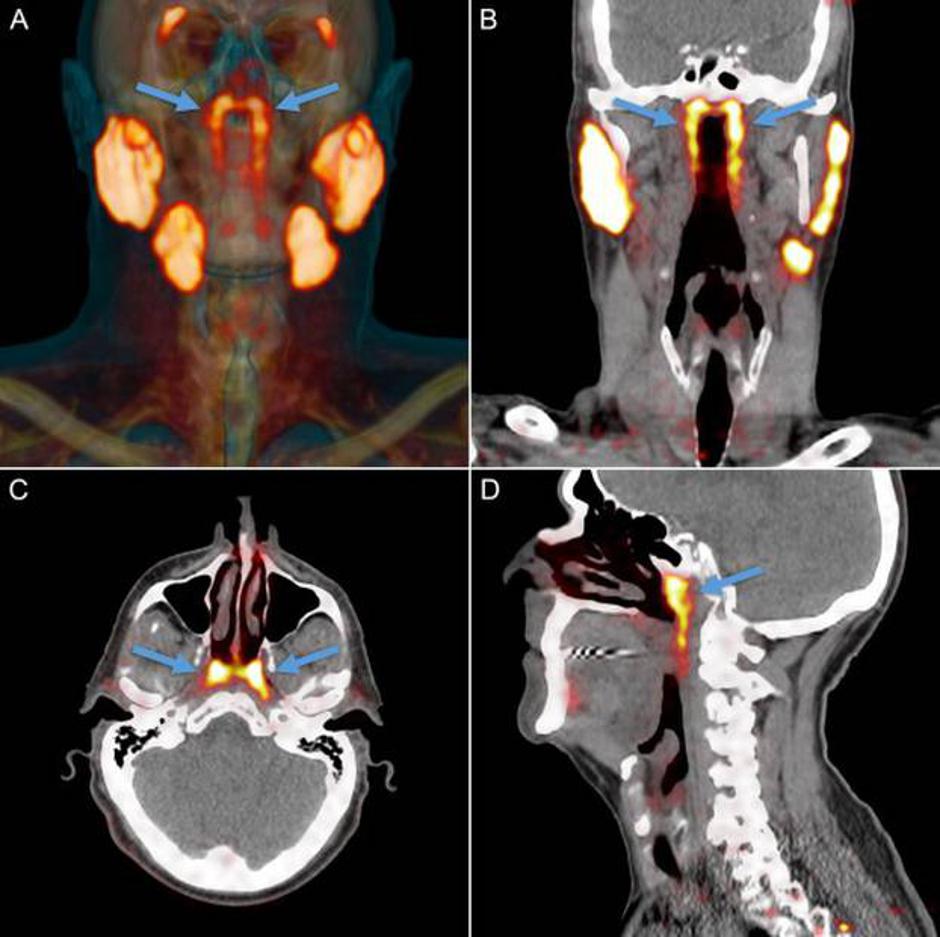

Onkolozi Netherlands Cancer Institute koristili su nove vrste pretraga u pregledu glave kod pacijenata s rakom glave i vrata. Kod oboljelih od raka prostate koristili su pozitronsku emisijsku tomografiju poznatiju kao PET scan uz antigene, a to se pokazalo učinkovitim u praćenju širenja raka prostate tijelom. Pacijenti prije pretrage dobiju injekciju radioaktivne glukoze koja obasja tumor unutar tijela koji se tako bolje vidi.

Tijekom takve pretrage znanstvenici su primijetili dva područja u glavi koja su iznenada počela svijetliti. Nastavili su s pretragama i na drugim pacijentima te su ustanovili da se isto područje uključuje kod svih oboljelih. Najmanje 100 pacijenata imalo je isti nalaz. No to nije anomalija, nego potpuno novi organ.

Svoje otkriće opisali su za stručni časopis Radiotherapy and Oncology te su objasnili kako je riječ o paru žlijezda slinovnica koje se nalaze u stražnjoj strani nazofarinksa.

Tim je svoje otkriće potvrdio s kolegama u Amsterdamu te su istražili novi organ i na truplima. Nazvali su ga "tubularne žlijezde" zbog njihova položaja. Upravo smještaj tih žlijezda u glavi mogao bi biti problem za pacijente koji idu na zračenje kod kojih se javlja problem s gutanjem. Spoznaja da te žlijezde postoje mogla bi pomoći onkolozima da ciljanom terapijom izbjegavaju to mjesto i preveniraju moguće komplikacije.